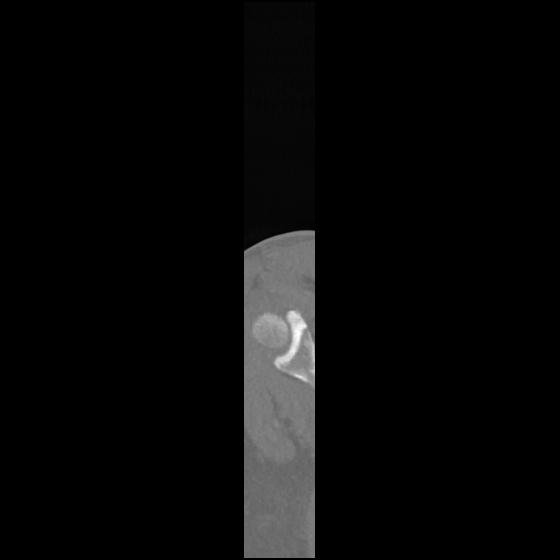

24 ANGIO,CE,Sag-MIP,5.000,ANGIO,Sag-MIP,